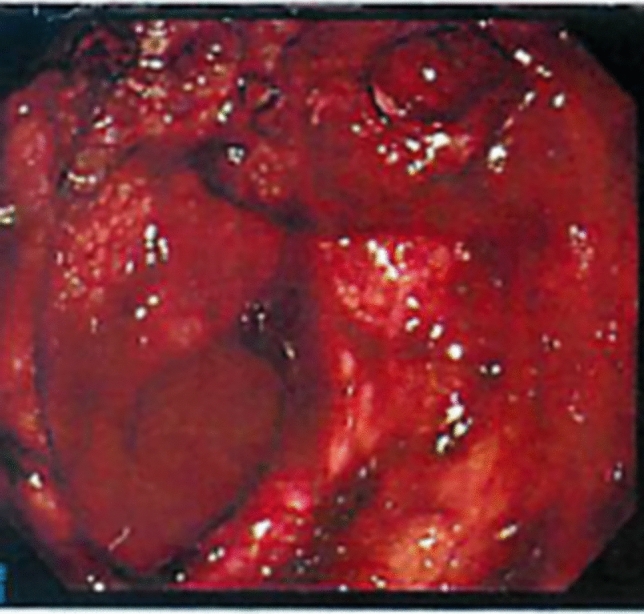

虽然有报道称止血放疗是治疗胃癌出血的有效方法,但其作用机制和即时效果尚不清楚。我们报告了一个胃癌出血的病例,这是由整个胃肿瘤和左侧胃动脉假性动脉瘤在肿瘤相关溃疡处引起的。患者因全胃肿瘤出血行放射治疗,随后经导管动脉栓塞治疗左胃动脉假性动脉瘤。放疗后2小时单段8 Gy x线造影显示,栓塞后的胃左动脉、未栓塞的胃右动脉、胃左动脉和肝左动脉总干的肿瘤血管和肿瘤染色均消失,推测未栓塞动脉的这些血管造影改变反映了止血放疗的即时效果。止血治疗后,患者生命体征稳定,血红蛋白水平未下降,提示立即止血。本病例提示止血机制与早期肿瘤血管改变有关,说明止血放疗可实现快速止血控制。因此,止血放疗应被视为胃癌出血的紧急治疗选择。

Although hemostatic radiotherapy has been reported as an effective treatment for gastric cancer bleeding, its mechanism and immediate effects remain unclear. We experienced a case of gastric cancer bleeding originating from both the whole gastric tumor and a left gastric arterial pseudoaneurysm at the tumor-associated ulcer. The patient was treated with radiotherapy for bleeding from the whole gastric tumor, followed by transcatheter arterial embolization for the left gastric arterial pseudoaneurysm. Angiography performed two hours after radiotherapy with an X-ray of 8 Gy in a single fraction revealed the disappearance of both tumor vessels and tumor stain from not only the embolized left gastric artery but also both the non-embolized right gastric artery and common trunk of the left gastric and the left hepatic arteries, which indicated these angiographic changes of the non-embolized arteries were presumed to reflect an immediate effect of hemostatic radiotherapy. Following hemostatic treatments, the patient's vital signs stabilized, and hemoglobin levels did not decrease, indicating immediate hemostasis. This case suggests a link between hemostatic mechanism and early tumor vessel changes, indicating that hemostatic radiotherapy can achieve rapid bleeding control. Therefore, hemostatic radiotherapy should be considered an emergency treatment option for gastric cancer bleeding.